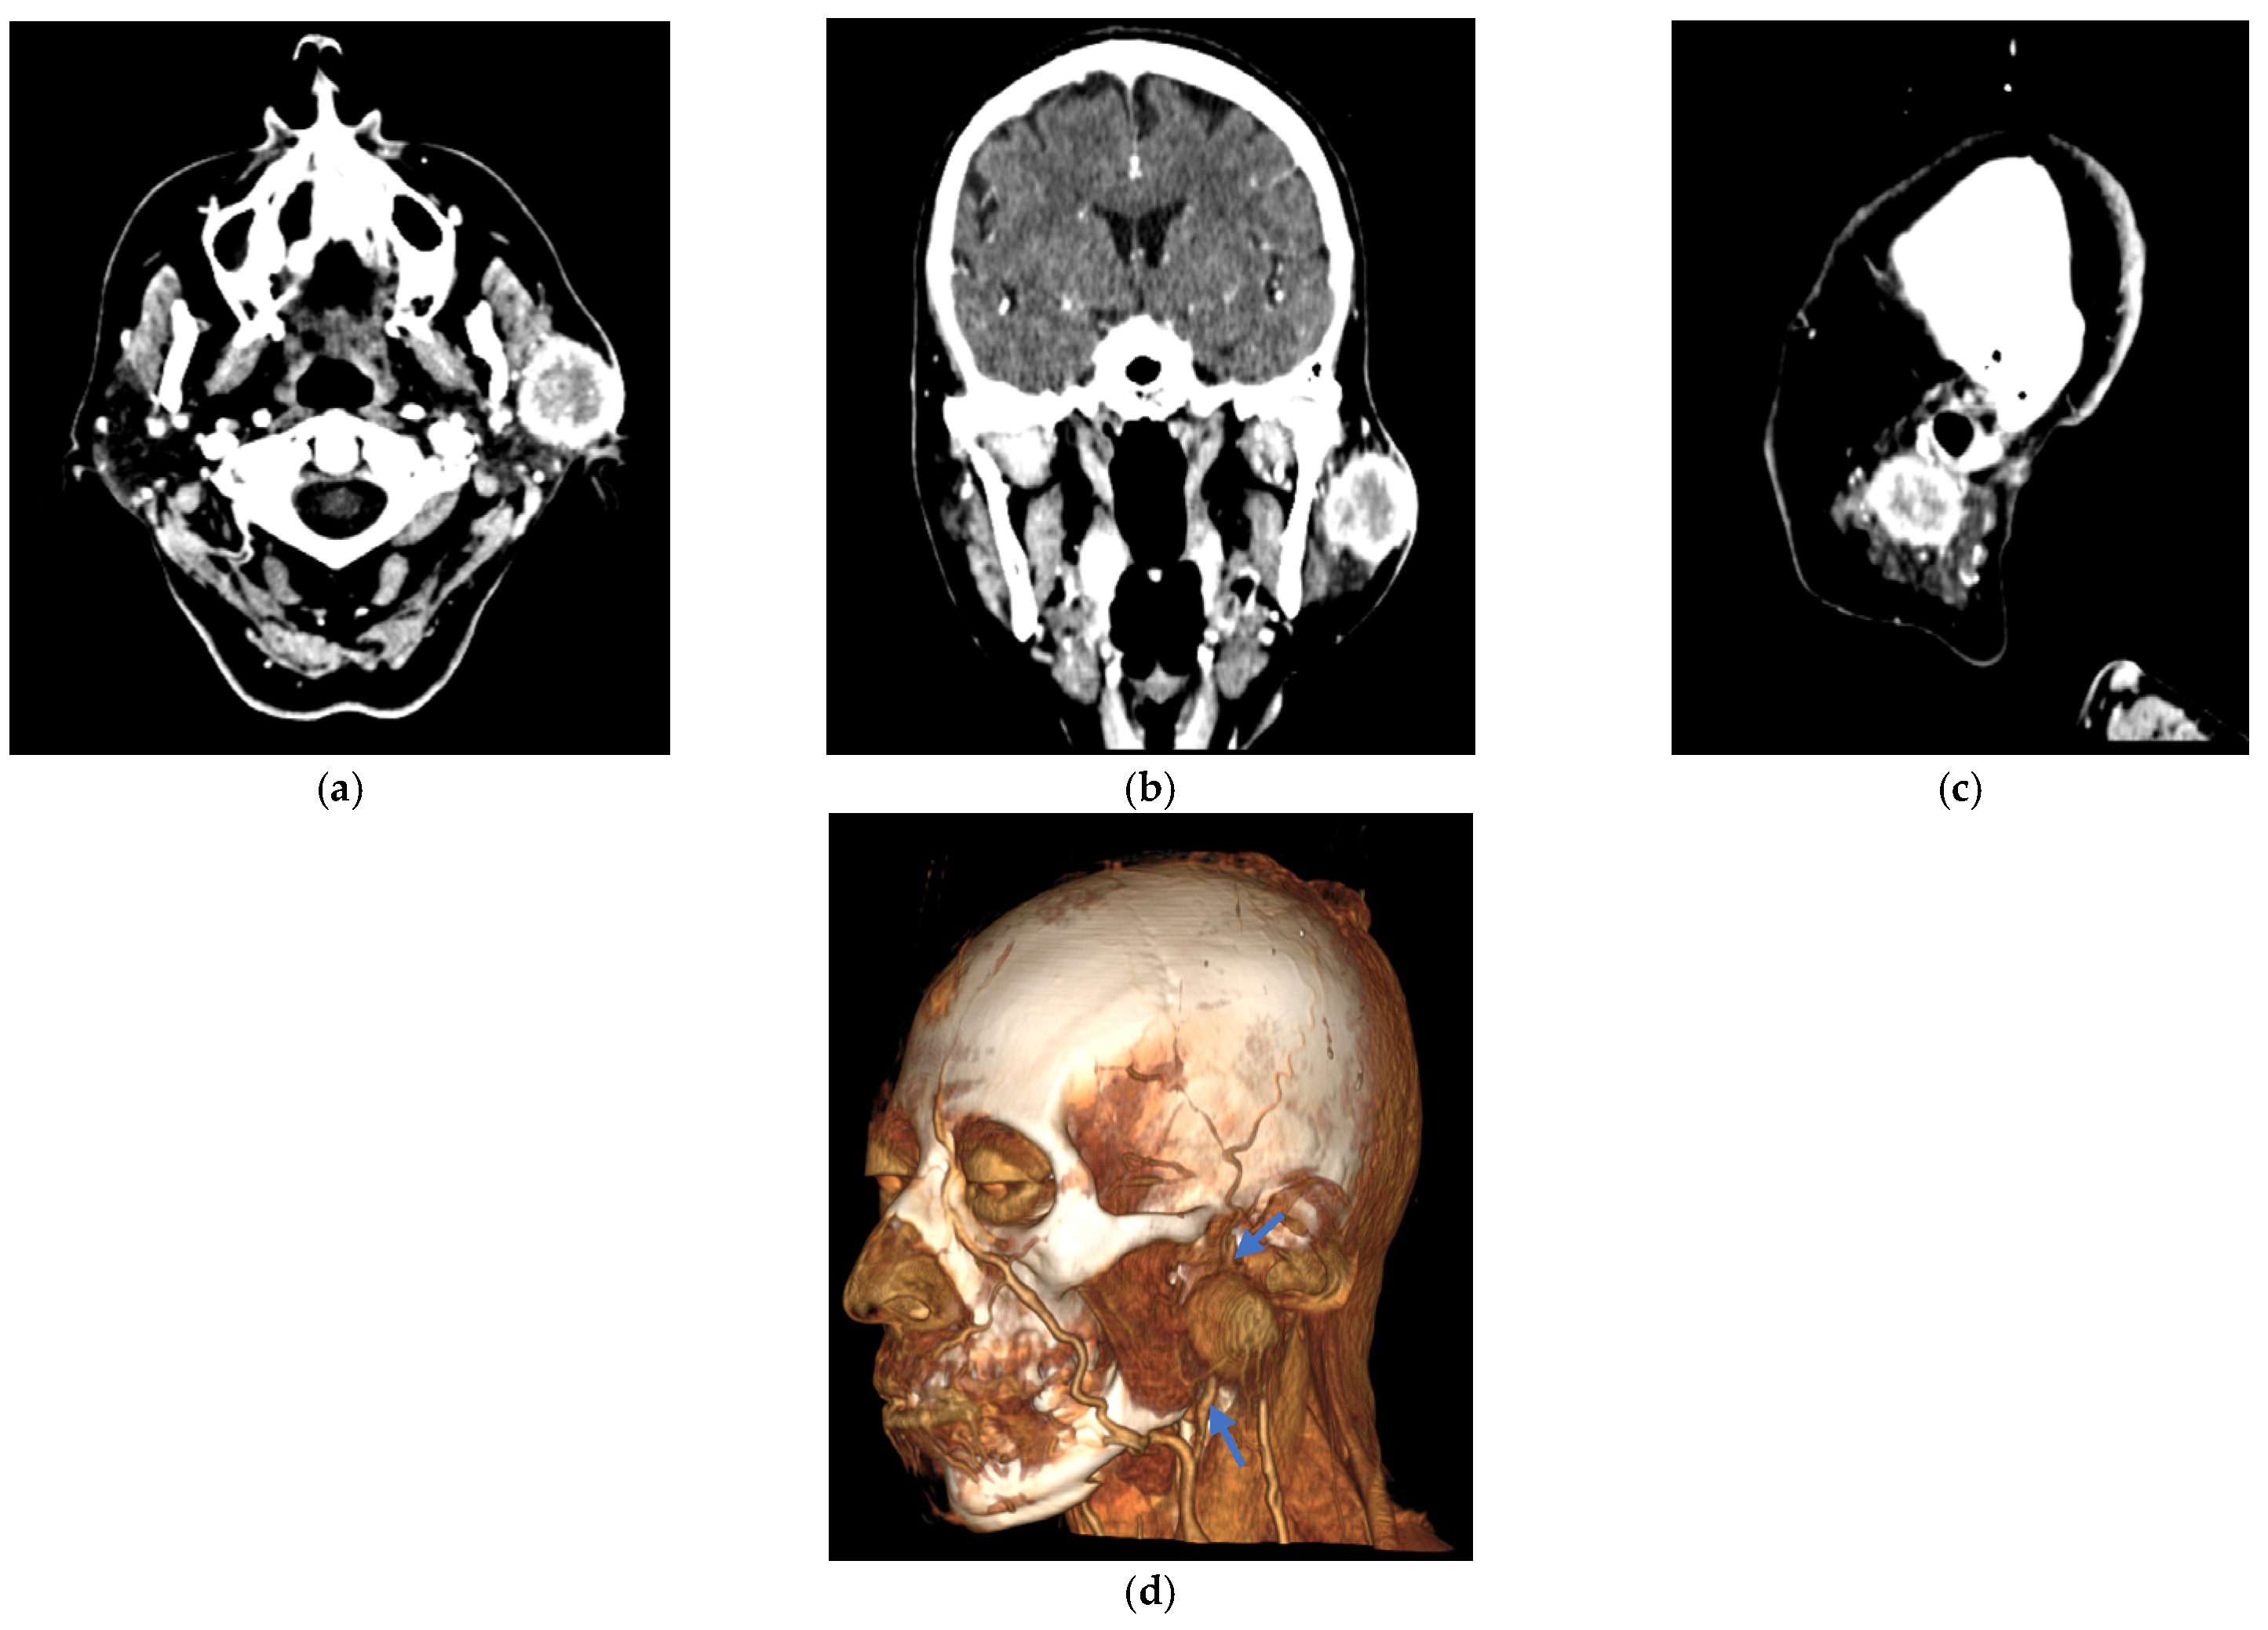

| T0 (imaging) | Contrast-enhanced head/neck CT | Well-defined nodule 30 × 30 mm in the left parotid with avid enhancement. |